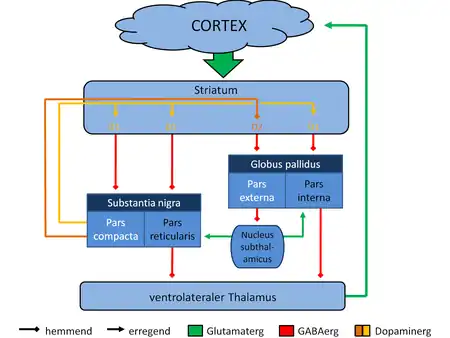

[31] The largest connection is from the cortex, in terms of cell axons. Many parts of the neocortex innervate the dorsal striatum. The cortical pyramidal neurons projecting to the striatum are located in layers II-VI, with the most dense projections come from layer V.[32] They end mainly on the dendritic spines of the spiny neurons. They are glutamatergic, exciting striatal neurons.

Another well-known afferent is the nigrostriatal connection arising from the neurons of the substantia nigra pars compacta. While cortical axons synapse mainly on spine heads of spiny neurons, nigral axons synapse mainly on spine shafts. In primates, the thalamostriatal afferent comes from the central median-parafascicular complex of the thalamus (see primate basal ganglia system). This afferent is glutamatergic. The participation of truly intralaminar neurons is much more limited. The striatum also receives afferents from other elements of the basal ganglia such as the subthalamic nucleus (glutamatergic) or the external globus pallidus (GABAergic).

The primary outputs of the ventral striatum project to the ventral pallidum, then the medial dorsal nucleus of the thalamus, which is part of the frontostriatal circuit. Additionally, the ventral striatum projects to the globus pallidus, and substantia nigra pars reticulata. Some of its other outputs include projections to the extended amygdala, lateral hypothalamus, and pedunculopontine nucleus.[36]

The main nucleus of the basal ganglia is the striatum which projects directly to the globus pallidus via a pathway of striatopallidal fibers.[37] The striato-pallidal pathway has a whitish appearance due to the myelinated fibers. This projection comprises successively the external globus pallidus (GPe), the internal globus pallidus (GPi), the pars compacta of the substantia nigra (SNc), and the pars reticulata of substantia nigra (SNr). The neurons of this projection are inhibited by GABAergic synapses from the dorsal striatum. Among these targets, the GPe does not send axons outside the system. Others send axons to the superior colliculus. Two others comprise the output to the thalamus, forming two separate channels: one through the internal segment of the globus pallidus to the ventral oralis nuclei of the thalamus and from there to the cortical supplementary motor area and another through the substantia nigra to the ventral anterior nuclei of the thalamus and from there to the frontal cortex and the occulomotor cortex.